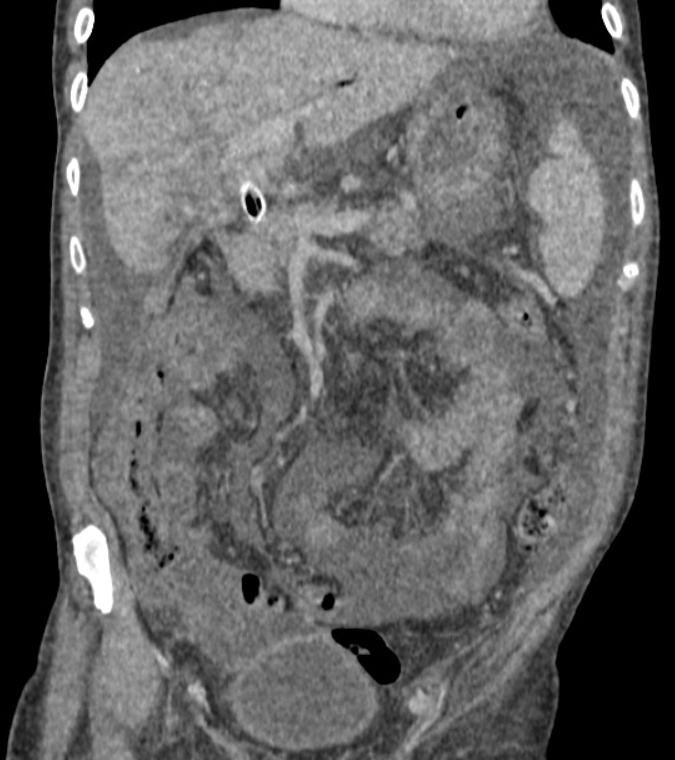

Feminino,67 anos, apresentando dor abdominal difusa, associada à perda ponderal e ascite.

Carcinomatose Peritoneal

Os implantes peritoneais são massas de tecidos moles que aparecem como nódulos solitários ou múltiplos. Os nódulos podem coalescer para formar placas que revestem as vísceras. Essas placas aparecem como áreas de espessamento irregular dos tecidos moles. Grandes placas omentais são chamadas de bolos omentais (omental cake). Os implantes podem realçar com o contraste intravenoso e podem calcificar. Alguns implantes são de baixa atenuação e mimetizam fluido loculado. Os locais comuns de metástases incluem hemidiafragma direito, fígado, calha paracólica direita, intestino, omento e pelve.

No abdome, os implantes na superfície diafragmática aparecem como espessamento nodular ou semelhante a placa do diafragma. O envolvimento do fígado e do baço resulta em recorte da superfície por massas com menor atenuação do que o parênquima em exames com contraste. Os ligamentos falciforme, gastro-hepático e gastroesplênico podem parecer espessados e mostrar encalhe de tecidos moles. Os tumores podem ser vistos na porta hepática, fossa da vesícula biliar e saco menor e na superfície do estômago. Espessamento irregular e nodularidade ocorrem nas goteiras paracólicas. Há infiltração da gordura omental por tumor de atenuação de tecidos moles. Nódulos discretos também podem estar presentes e podem ser distinguidos do intestino porque não estão conectados às alças adjacentes. Massas de tecidos moles no intestino e no mesentério podem aderir as alças e causar obstrução intestinal. A obstrução intestinal é o tipo mais comum de morbidade secundária ao câncer de ovário, ocorrendo em 51% dos casos. As lesões mesentéricas aparecem como espessamento da raiz com um padrão estrelado e irradiado. A extensão da doença omental para a parede abdominal anterior resulta em massas periumbilicais.

Na pelve, os implantes podem envolver a superfície superior do sigmóide, o mesocólon sigmóide, os ligamentos uterossacrais laterais ao reto e a parede lateral pélvica, bexiga, fundo de saco, reto e canais inguinais. Semelhantes aos do abdome, esses implantes aparecem como espessamento e massas de partes moles.